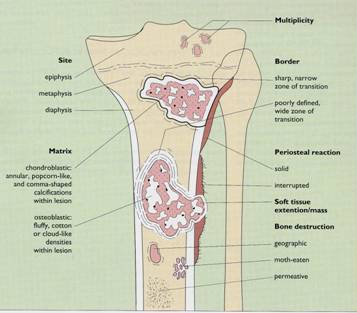

Proceduri diagnostice:

- radiografii osoase: osteoliza,

osteoscleroza sau lez mixte, reactie periostala, distructie corticala

- CT & RMN apreciaza extinderea os si

extracompartimentala a tu

TO: Benign vs Malign

TO: Clasificarea TO